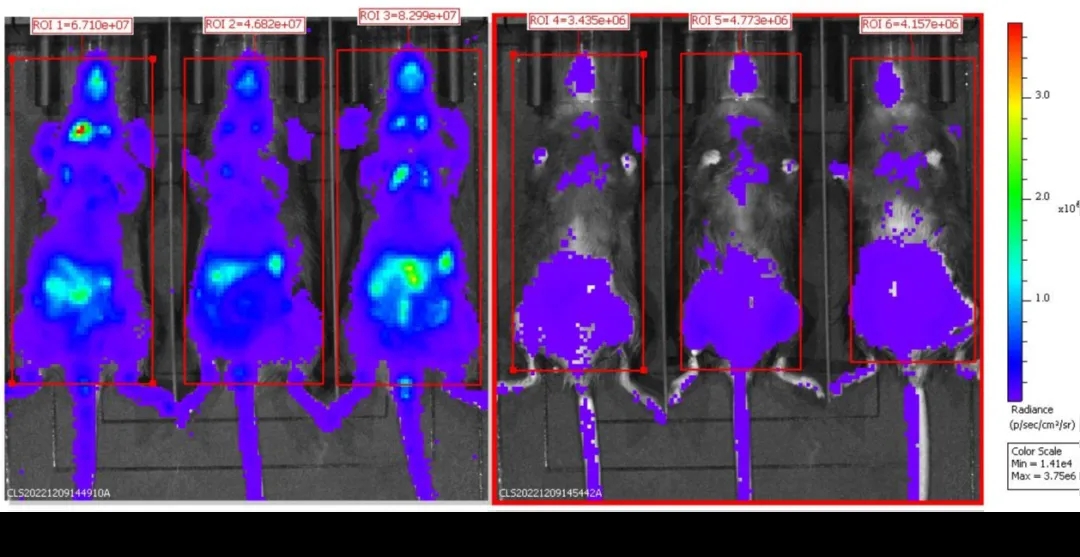

B-Foxp3-EGFP-DTR-Luc小鼠注射DT后BLI分析

连续两天注射PBS(n=3)或DT(n=3)的B-Foxp3-EGFP-DTR-Luc小鼠被麻醉后进行生物发光成像。小鼠静脉注射 150mg/kg的D-Lucifenrin钾盐10分钟后,使用IVIS Lumina LT Inst Series III进行成像。

结果显示,B-Foxp3-EGFP-DTR-Luc小鼠的Treg细胞比例与野生型小鼠相当;只在Foxp3-EGFP-DTR-Luc小鼠的CD4+和CD25+细胞群中检测到EGFP,可作为体内Treg细胞的标记物;此外,生物发光成像也可用于追踪Tregs细胞,注射DT后,Treg细胞在EGFP、Foxp3和生物发光成像水平上都显著减少。